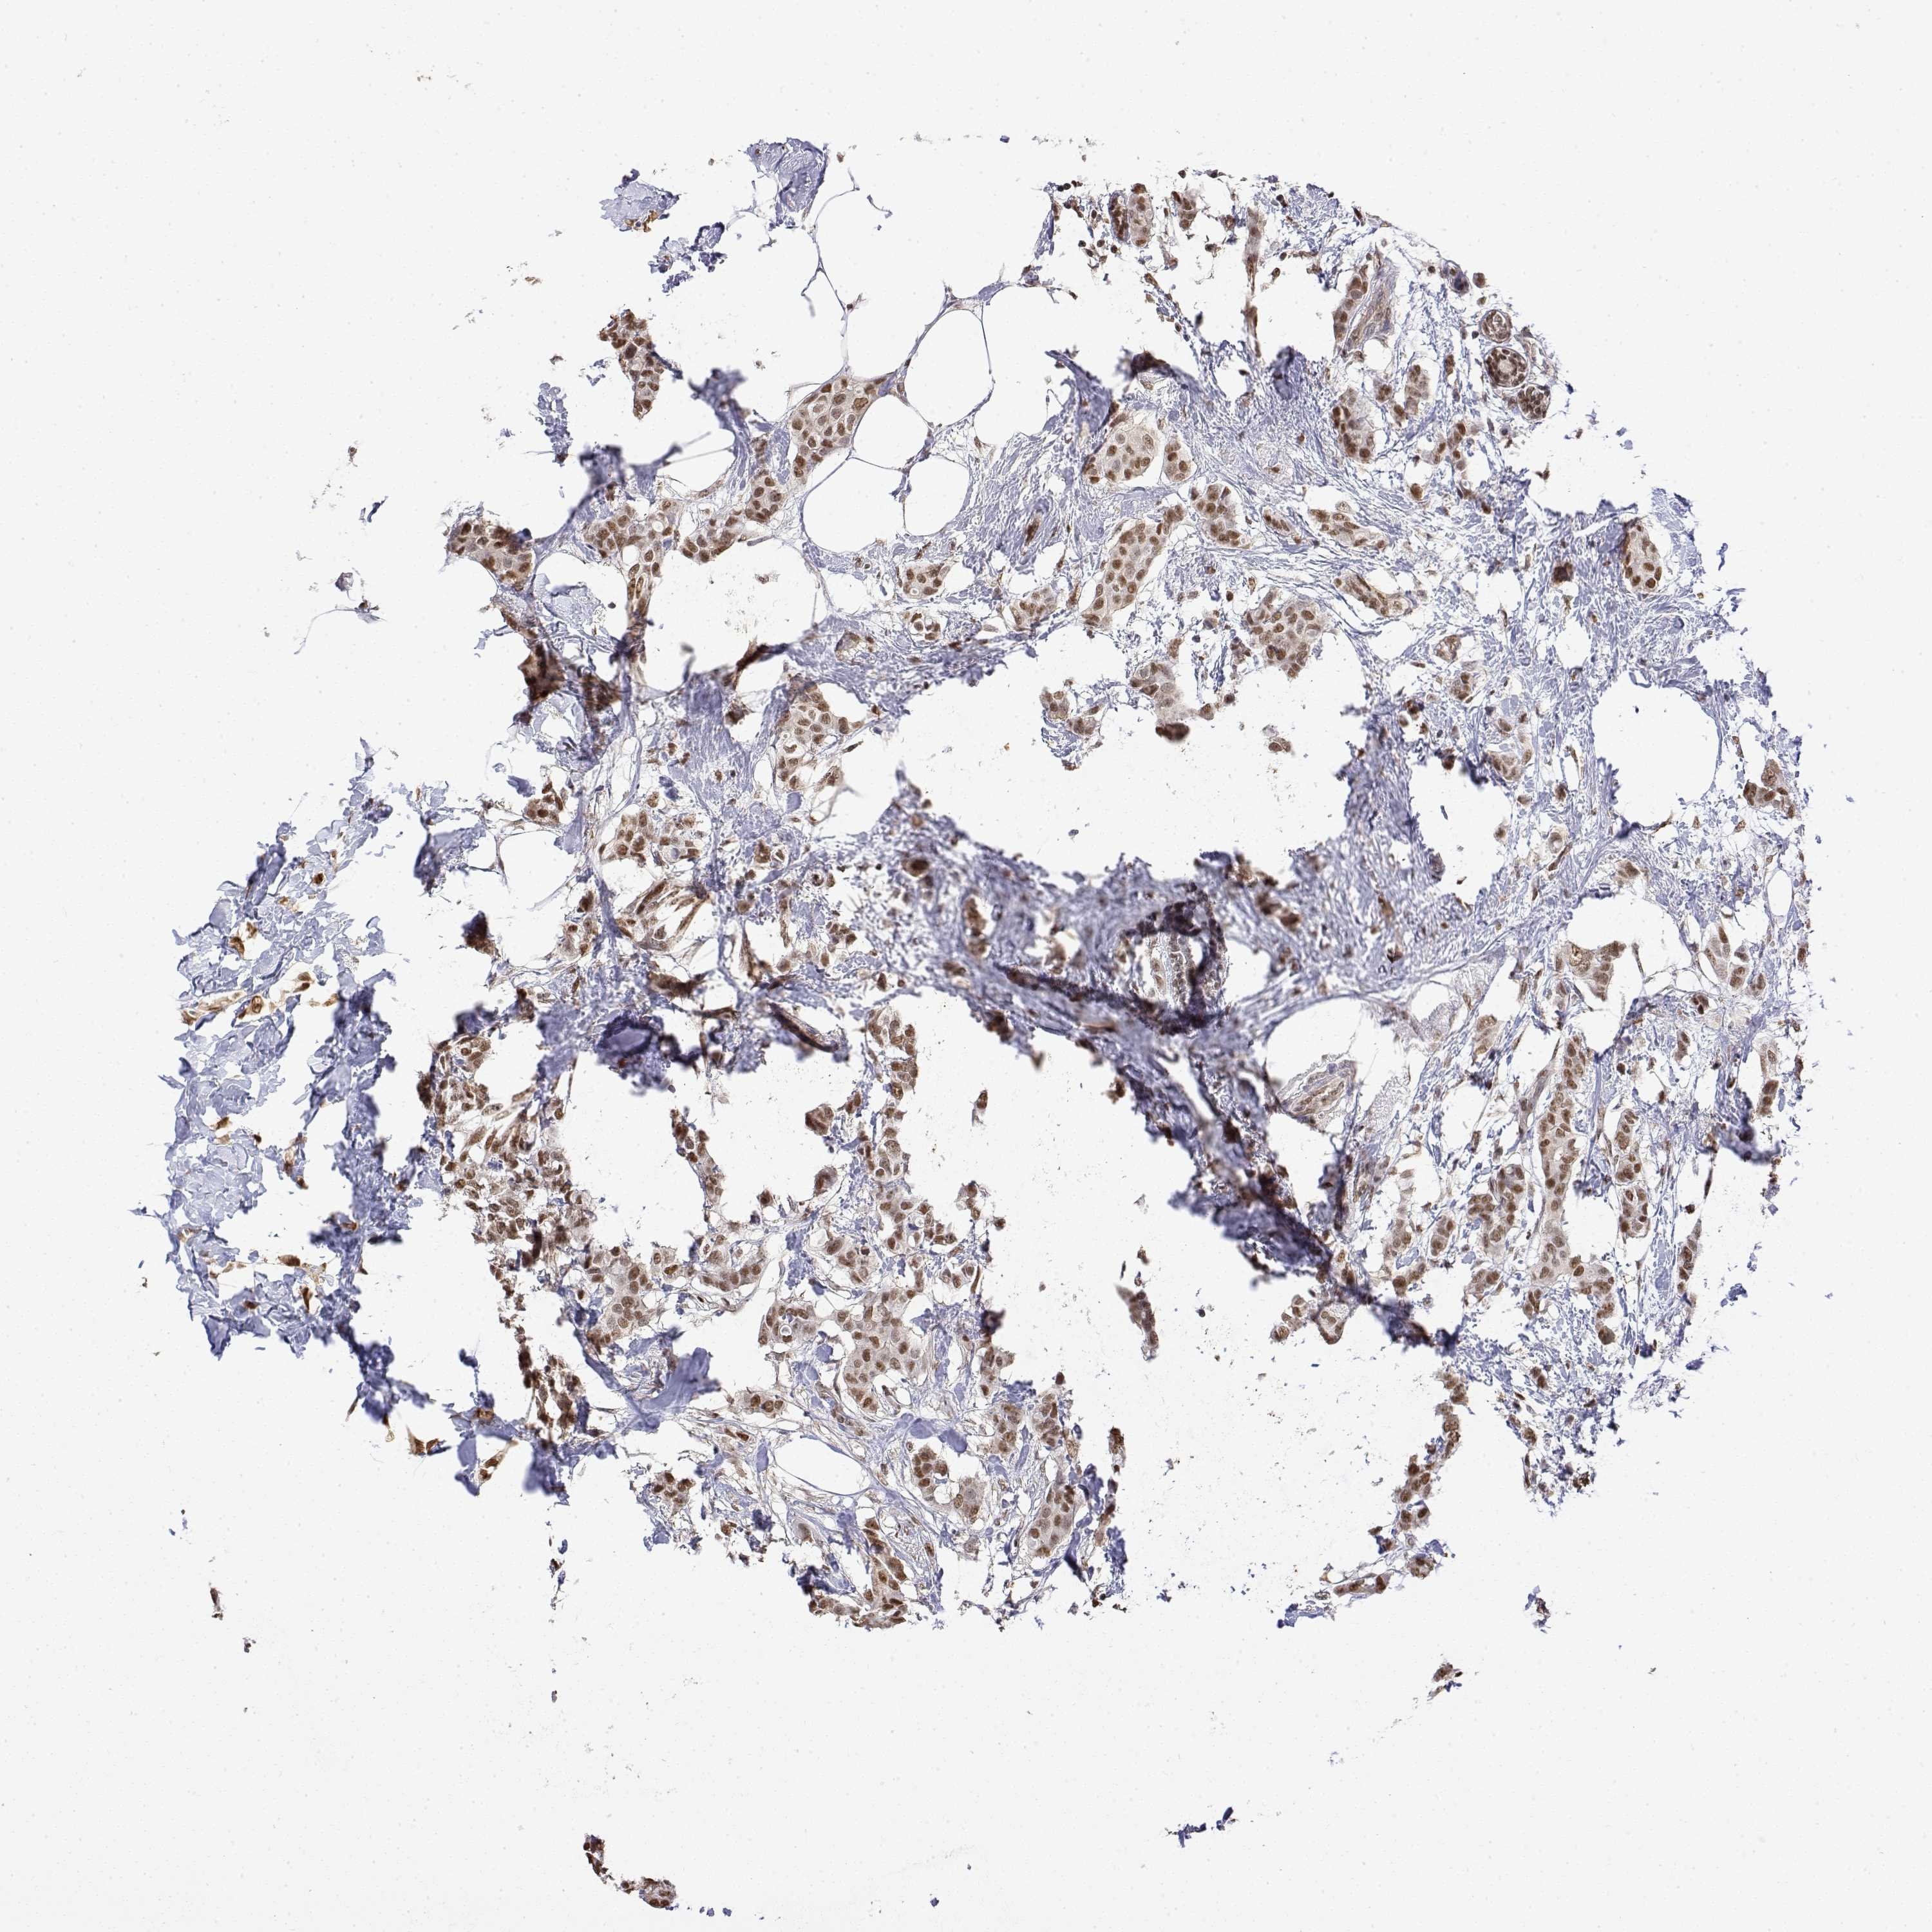

BRCA TCGA BRCA VALIDATION PROTEIN EXPRESSION